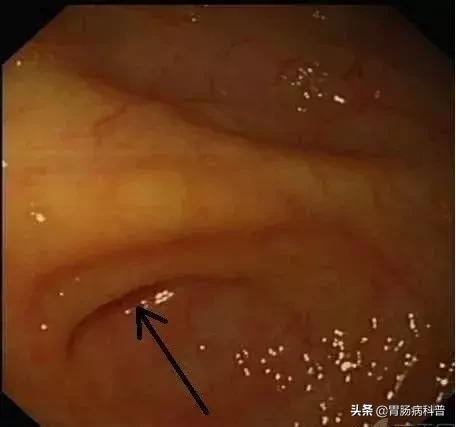

ERAT术后 内镜下观察阑尾的恢复情况良好,水肿消失。

A图示阑尾开口水肿消失(箭头);

B图示阑尾腔内黏膜光整(椭圆形线圈),无炎症表现。

图A

图B